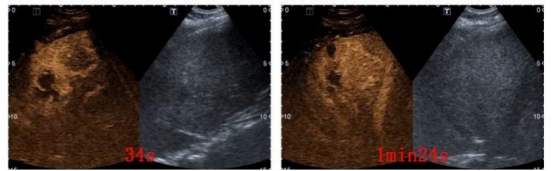

射频后病灶完全消融

杨秀华对葛某的肝脏进行全面扫查,共检出6枚病灶,分别位于肝S3、S5(与胆囊及门静脉分支位置近)、S6和S7(位置近膈肌、受气体干扰,且治疗过程易损伤),病灶多且位置刁钻成为了治疗的难点,如何在保证安全的前提下对全部病灶进行治疗,成为此次治疗的难题,杨秀华与李林强本着为患者谋求最大益处的治疗原则,决定为葛某行射频消融治疗,一次性消融全部病灶。术前杨秀华团队姜脉涛医生先在超声引导下为葛某建立人工胸水,在麻醉医生紧密配合下,杨秀华凭借丰富的治疗经验,精准布针,仅用2根射频针便完成6枚病灶的完全消融。